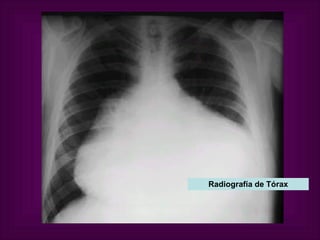

Aumento de tamaño de la silueta cardíaca  en presencia de derrame pericárdico importante  ( > 250 ml), con forma de «cantimplora».   Radiografía de Tórax

Radiografía de Tórax